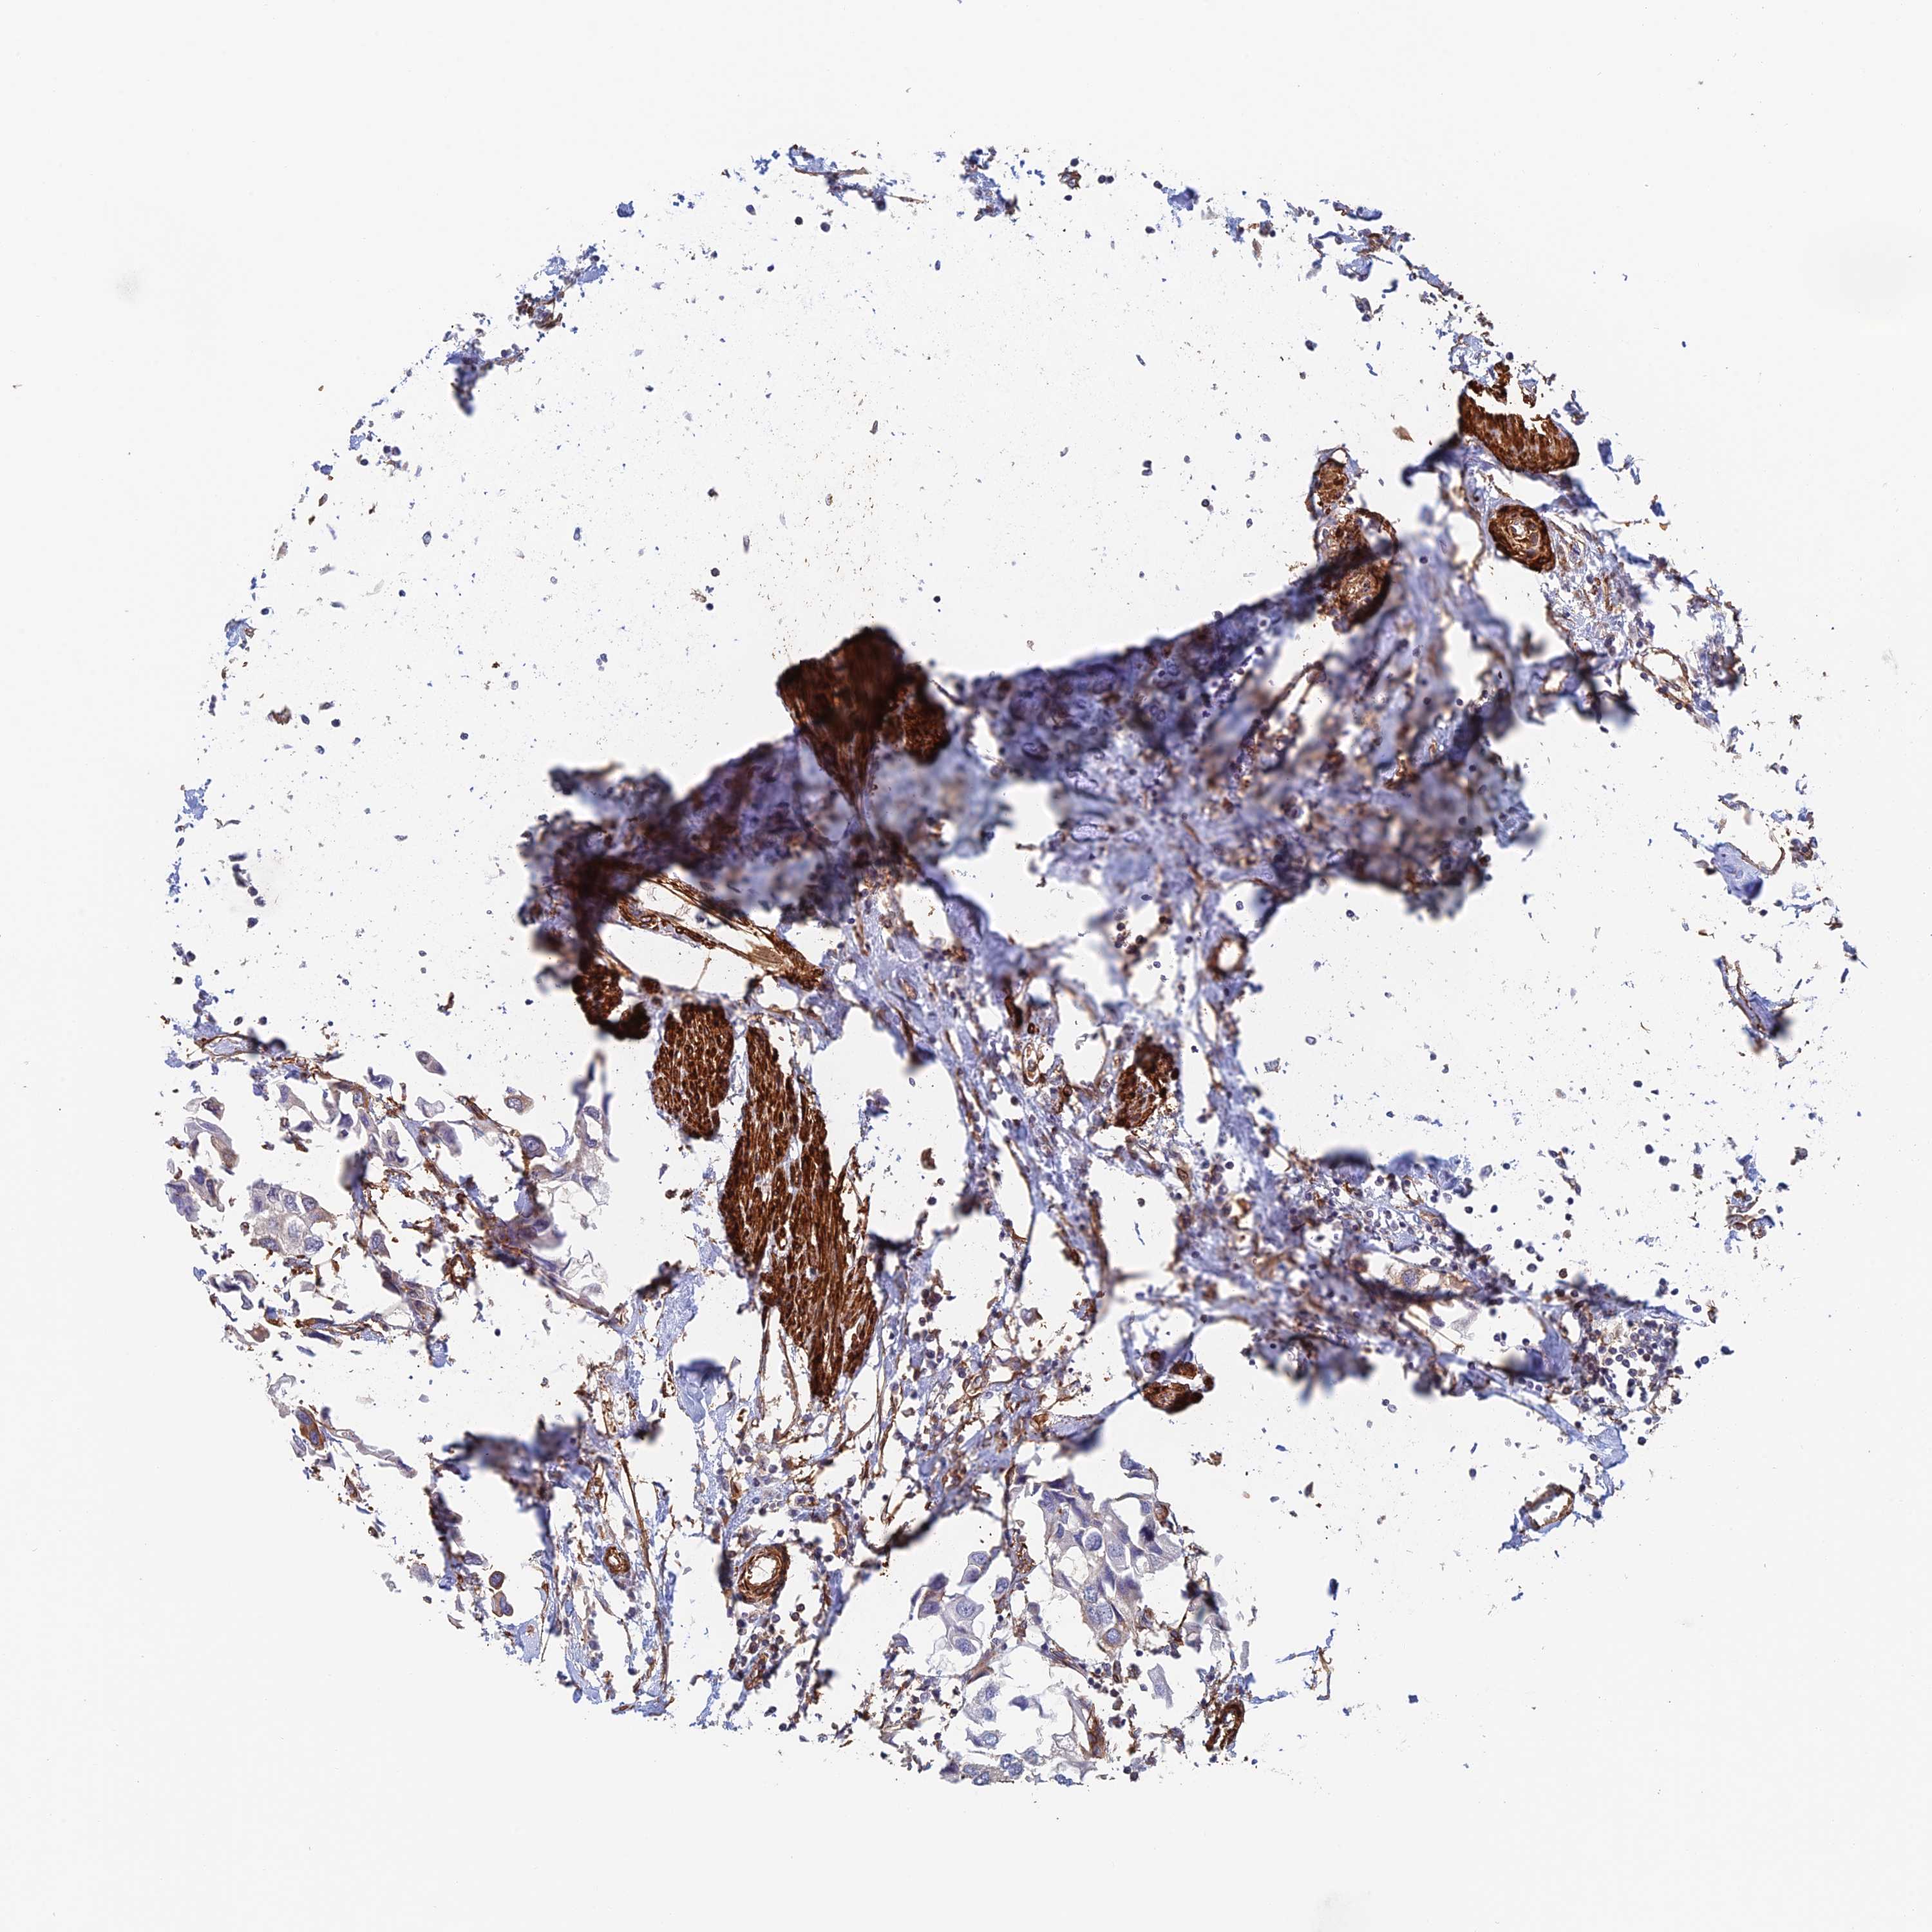

UROTHELIAL CANCER - Protein expressioni

A mouse-over function shows sample information and annotation data. Click on an image to view it in a full screen mode. Samples can be filtered based on level of antibody staining by selecting one or several of the following categories: high, medium, low and not detected. The assay and annotation is described here.

Antibody stainingi

Antibody staining in the annotated cell types in the current human tissue is reported as not detected, low, medium, or high, based on conventional immunohistochemistry profiling in selected tissues. This score is based on the combination of the staining intensity and fraction of stained cells.

Each image is clickable and will lead to virtual microscopy that enables deeper exploration of all samples and also displays staining intensity scores, fraction scores and subcellular localization as well as patient and tissue information for each sample.

Antibody CAB025747

Antibody CAB044670

Staining

High

Medium

Low

Not detected

Intensity

Strong

Moderate

Weak

Negative

Quantity

>75%

75%-25%

<25%

None

Location

Nuclear

Cytoplasmic/membranous

Cytoplasmic/membranous,nuclear

Urothelial carcinoma, Low grade

Urothelial carcinoma, High grade